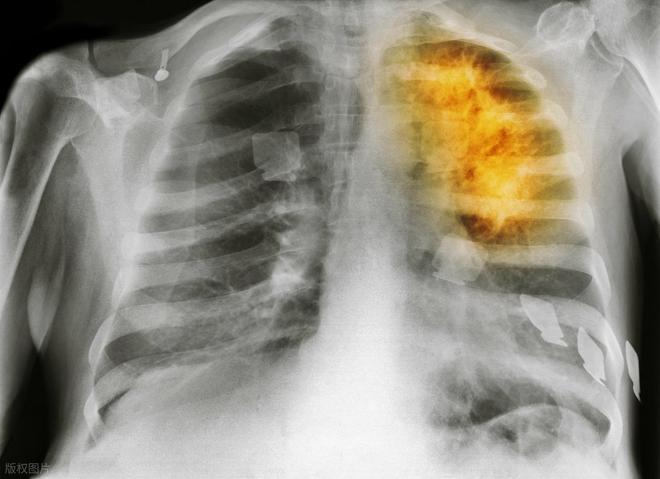

肺癌提前一年就有征兆?医生提醒:身体这3处变化别忽视

。早在确诊前的半年到一年,身体就可能发出信号。只是这些信号太隐蔽、太“不像大事”,总被我们忽略、误解、耽搁。

低剂量螺旋CT,是目前国际公认肺癌早筛的有效手段。特别适用于高危人群:长期吸烟、空气污染接触者、慢性肺部疾病患者、有肿瘤家族史者。

2022年《中华肿瘤杂志》一项研究指出,通过年度LDCT筛查,肺癌早期检出率可提高至68%以上,患者5年生存率从不足20%提升至60%以上。